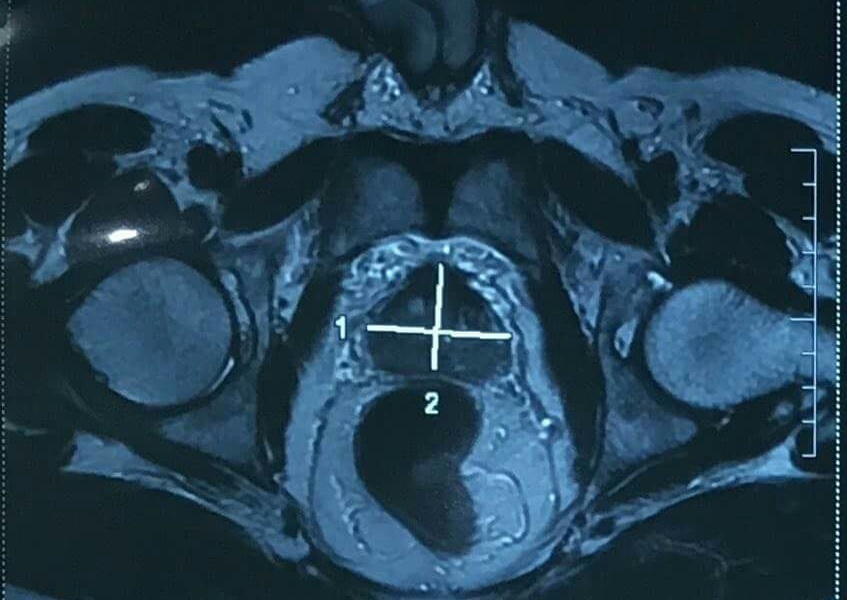

| Bướu tuyến tiền liệt trên người bệnh nhân. Ảnh: BSCC. |

Trước đó, bệnh nhân phát hiện bị ung thư. Sau khi được bác sĩ tư vấn, ông Vũ đã chọn phương pháp mổ bằng robot để cắt lọc tối đa mô ung thư.